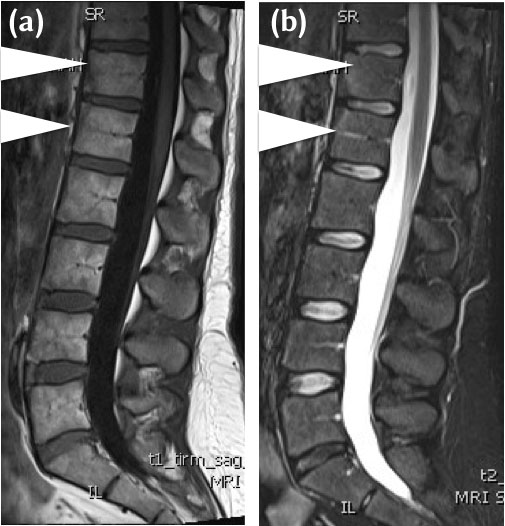

Figure 3

(a) 32-year-old female HLA b27 positive, with chronic low back pain and early morning stiffness. Mid sagittal T1-W MRI demonstrates triangular areas of heterogenous intermediate to low signal intensity to fat (between white arrowheads), vertebral corner lesions at T12 and LI. The features are of sclerosis and a Romanus’ Lesion on MRI. (b) 32-year-old female HLA b27 positive, with chronic low back pain and early morning stiffness. Mid sagittal STIR MRI demonstrates corresponding triangular areas of low signal intensity (between arrowheads) at T12/L1. The features are of sclerosis and a Romanus’ Lesion on MRI.